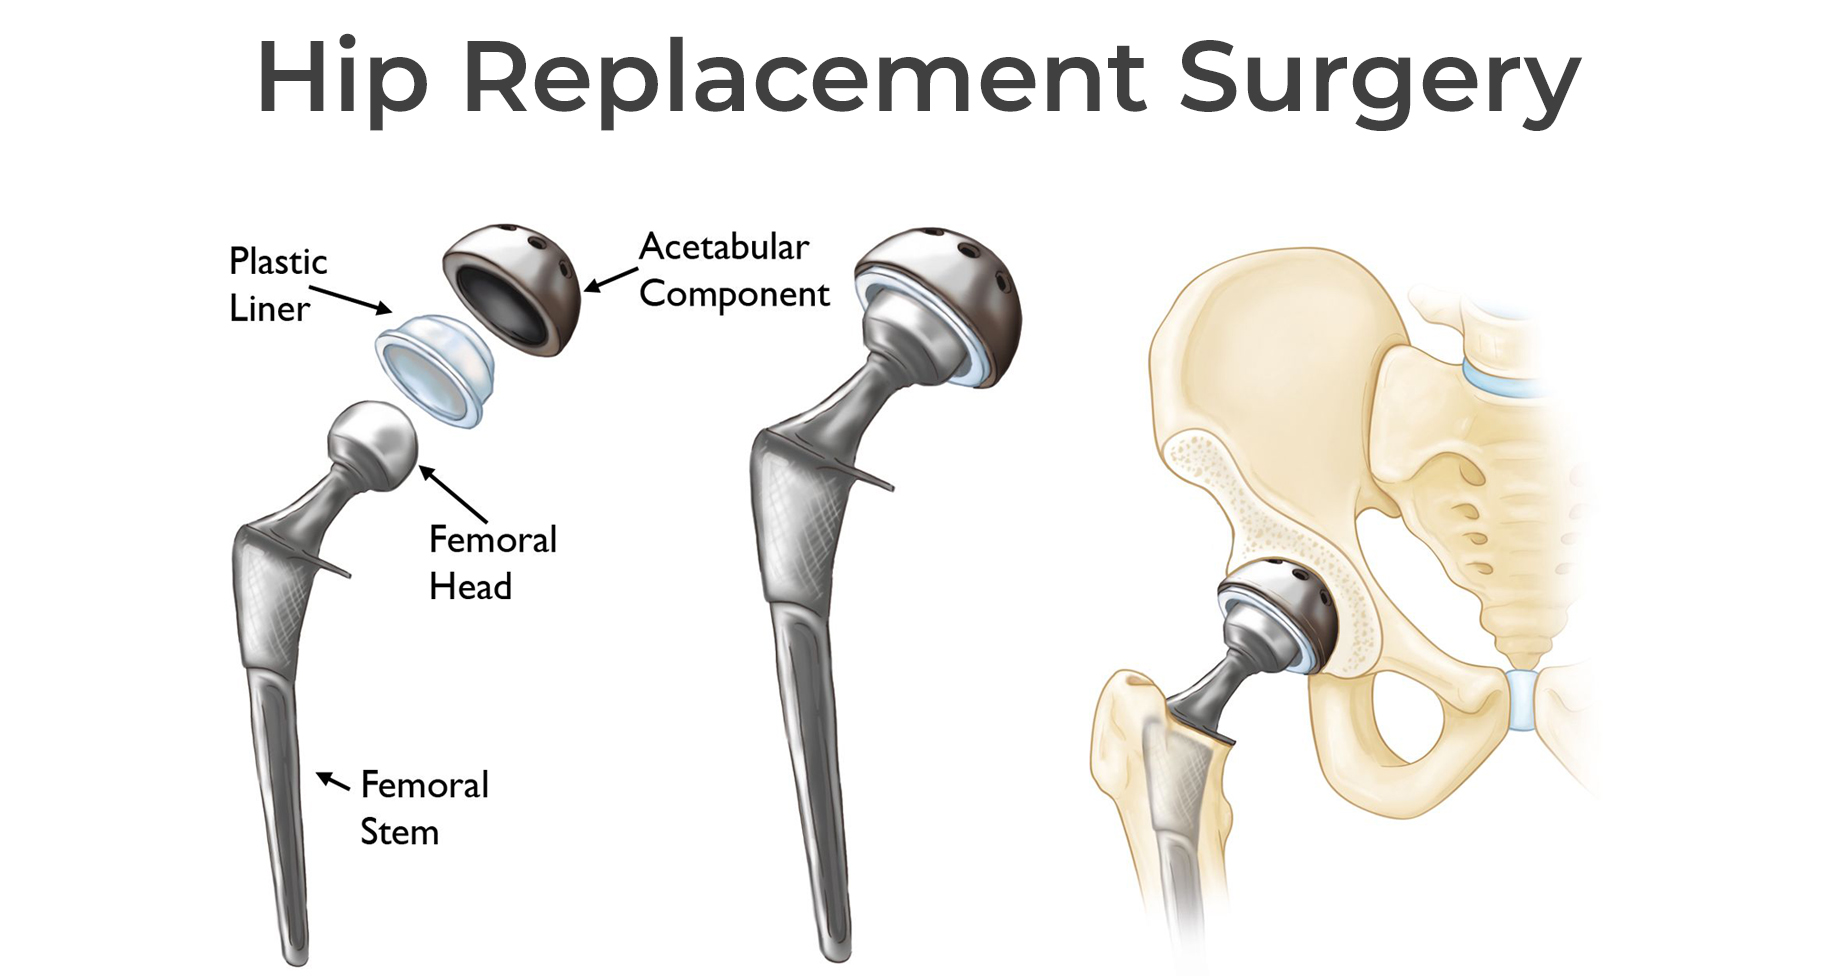

Замена таз сустава

Замена таз сустава 113 фотографий